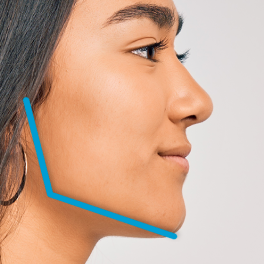

Brachyfacial

“Short” facial profiles with a low mandibular angle and deep overbite.